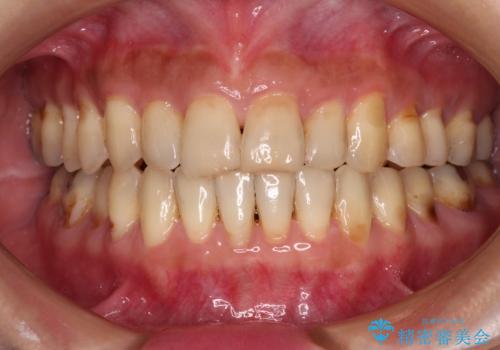

上下前歯が接触しない オープンバイトをインビザラインで改善

オープンバイト(開咬)を非抜歯インビザラインで治す